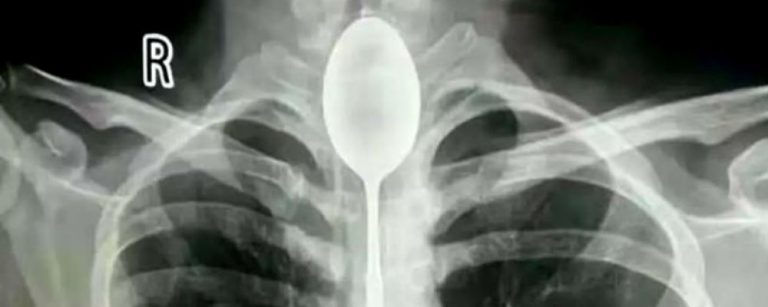

Es lo que ocurrió con un hombre de 26 años que llegó al Hospital General de Xinjiang Meikuang, en China, con una cuchara de 20 centímetros atorada en el esófago. Lo más curioso es que el objeto lo tenía alojado hace un año en su interior, según señala Daily Mail.

«Quedé impactado. Nunca he tenido algo así», dijo Yu Xiwu uno de los médicos que trató al paciente, el cual ya tenía complicaciones en su cuerpo lo que le había provocado una infección en esófago.

Según reconoció el paciente, de apellido Zhang, todo se debió a una apuesta que hizo con unos amigos, donde aseguró que era capaz de tragarse una cuchara. El hombre cumplió su palabra y lo hizo. El problema es que luego no pudo sacársela y anduvo un año con el objeto dentro de su cuerpo.

El hombre señaló que no había acudido antes al hospital porque en ningún momento le había molestado para hablar o comer. Sin embargo, un día recibió un golpe en el pecho lo que le provocó complicaciones derivadas a la cuchara que tenía en esófago.

Afortunadamente los médicos pudieron extraer la cuchara y el hombre se recupera satisfactoriamente.